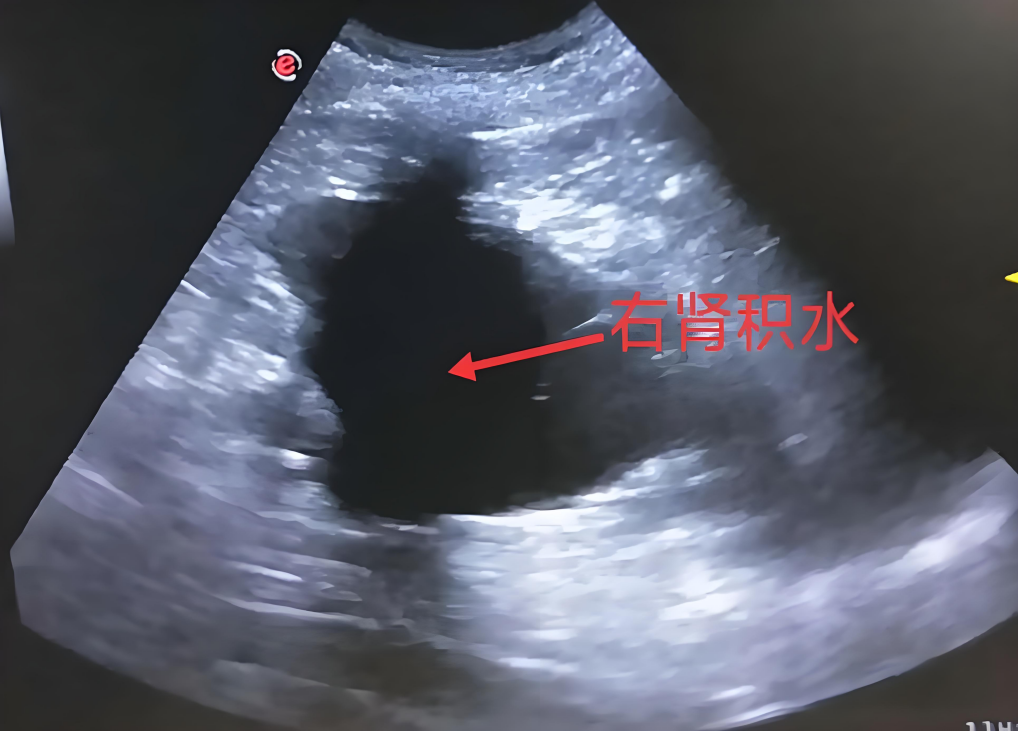

1、超聲檢查

超聲檢查對于腎積水的診斷簡直是超級厲害!它就像一個無形的“小偵探”,不需要給寶寶打針,也不會讓寶寶感到疼痛。檢查的時候,醫(yī)生只需要把一個小小的探頭在寶寶的肚子上輕輕移動,就能看到腎臟和泌尿系統(tǒng)的內(nèi)部情況。通過超聲,可以清楚地看到腎臟的大小、形狀以及積水的程度和范圍,為后續(xù)的診斷和治療提供重要的依據(jù)。